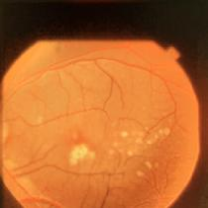

Figure 3: Three CFP fundus images with symptom of drusen and corresponding generated images. (a), (b), (c) Original images. (d), (e), (f) Generated images.

Style transferring neural network in [16] was modified to generate new disease images. This network adopts layers from ”conv1 1” to ”conv4 1” in pre-trained VGG-19 [24] network for the encoder, whose weights are provided by ImageNet-pretrained weights. What’s more, multi-level stylization strategy proposed in [16] is applied to optimize the VGG features in different layers. Input images are three CFP images and three FA images as style images shown in Fig. 2 and 5. Six CFP images with three drusen and three GA images in Fig. 3 and Fig. 4. Also, FA images are applied to generate new images in Fig. 6 and Fig. 7. For CFP images, six images are shown in Fig. 3 and in Fig. 4. In Fig. 3, generated images contain round, discrete yellow-white dots, which are the symptom of drusen. In the same way, in Fig. 4, well-demarcated areas appear on the three images. Therefore, style transferring can generate new retinal symptom images.